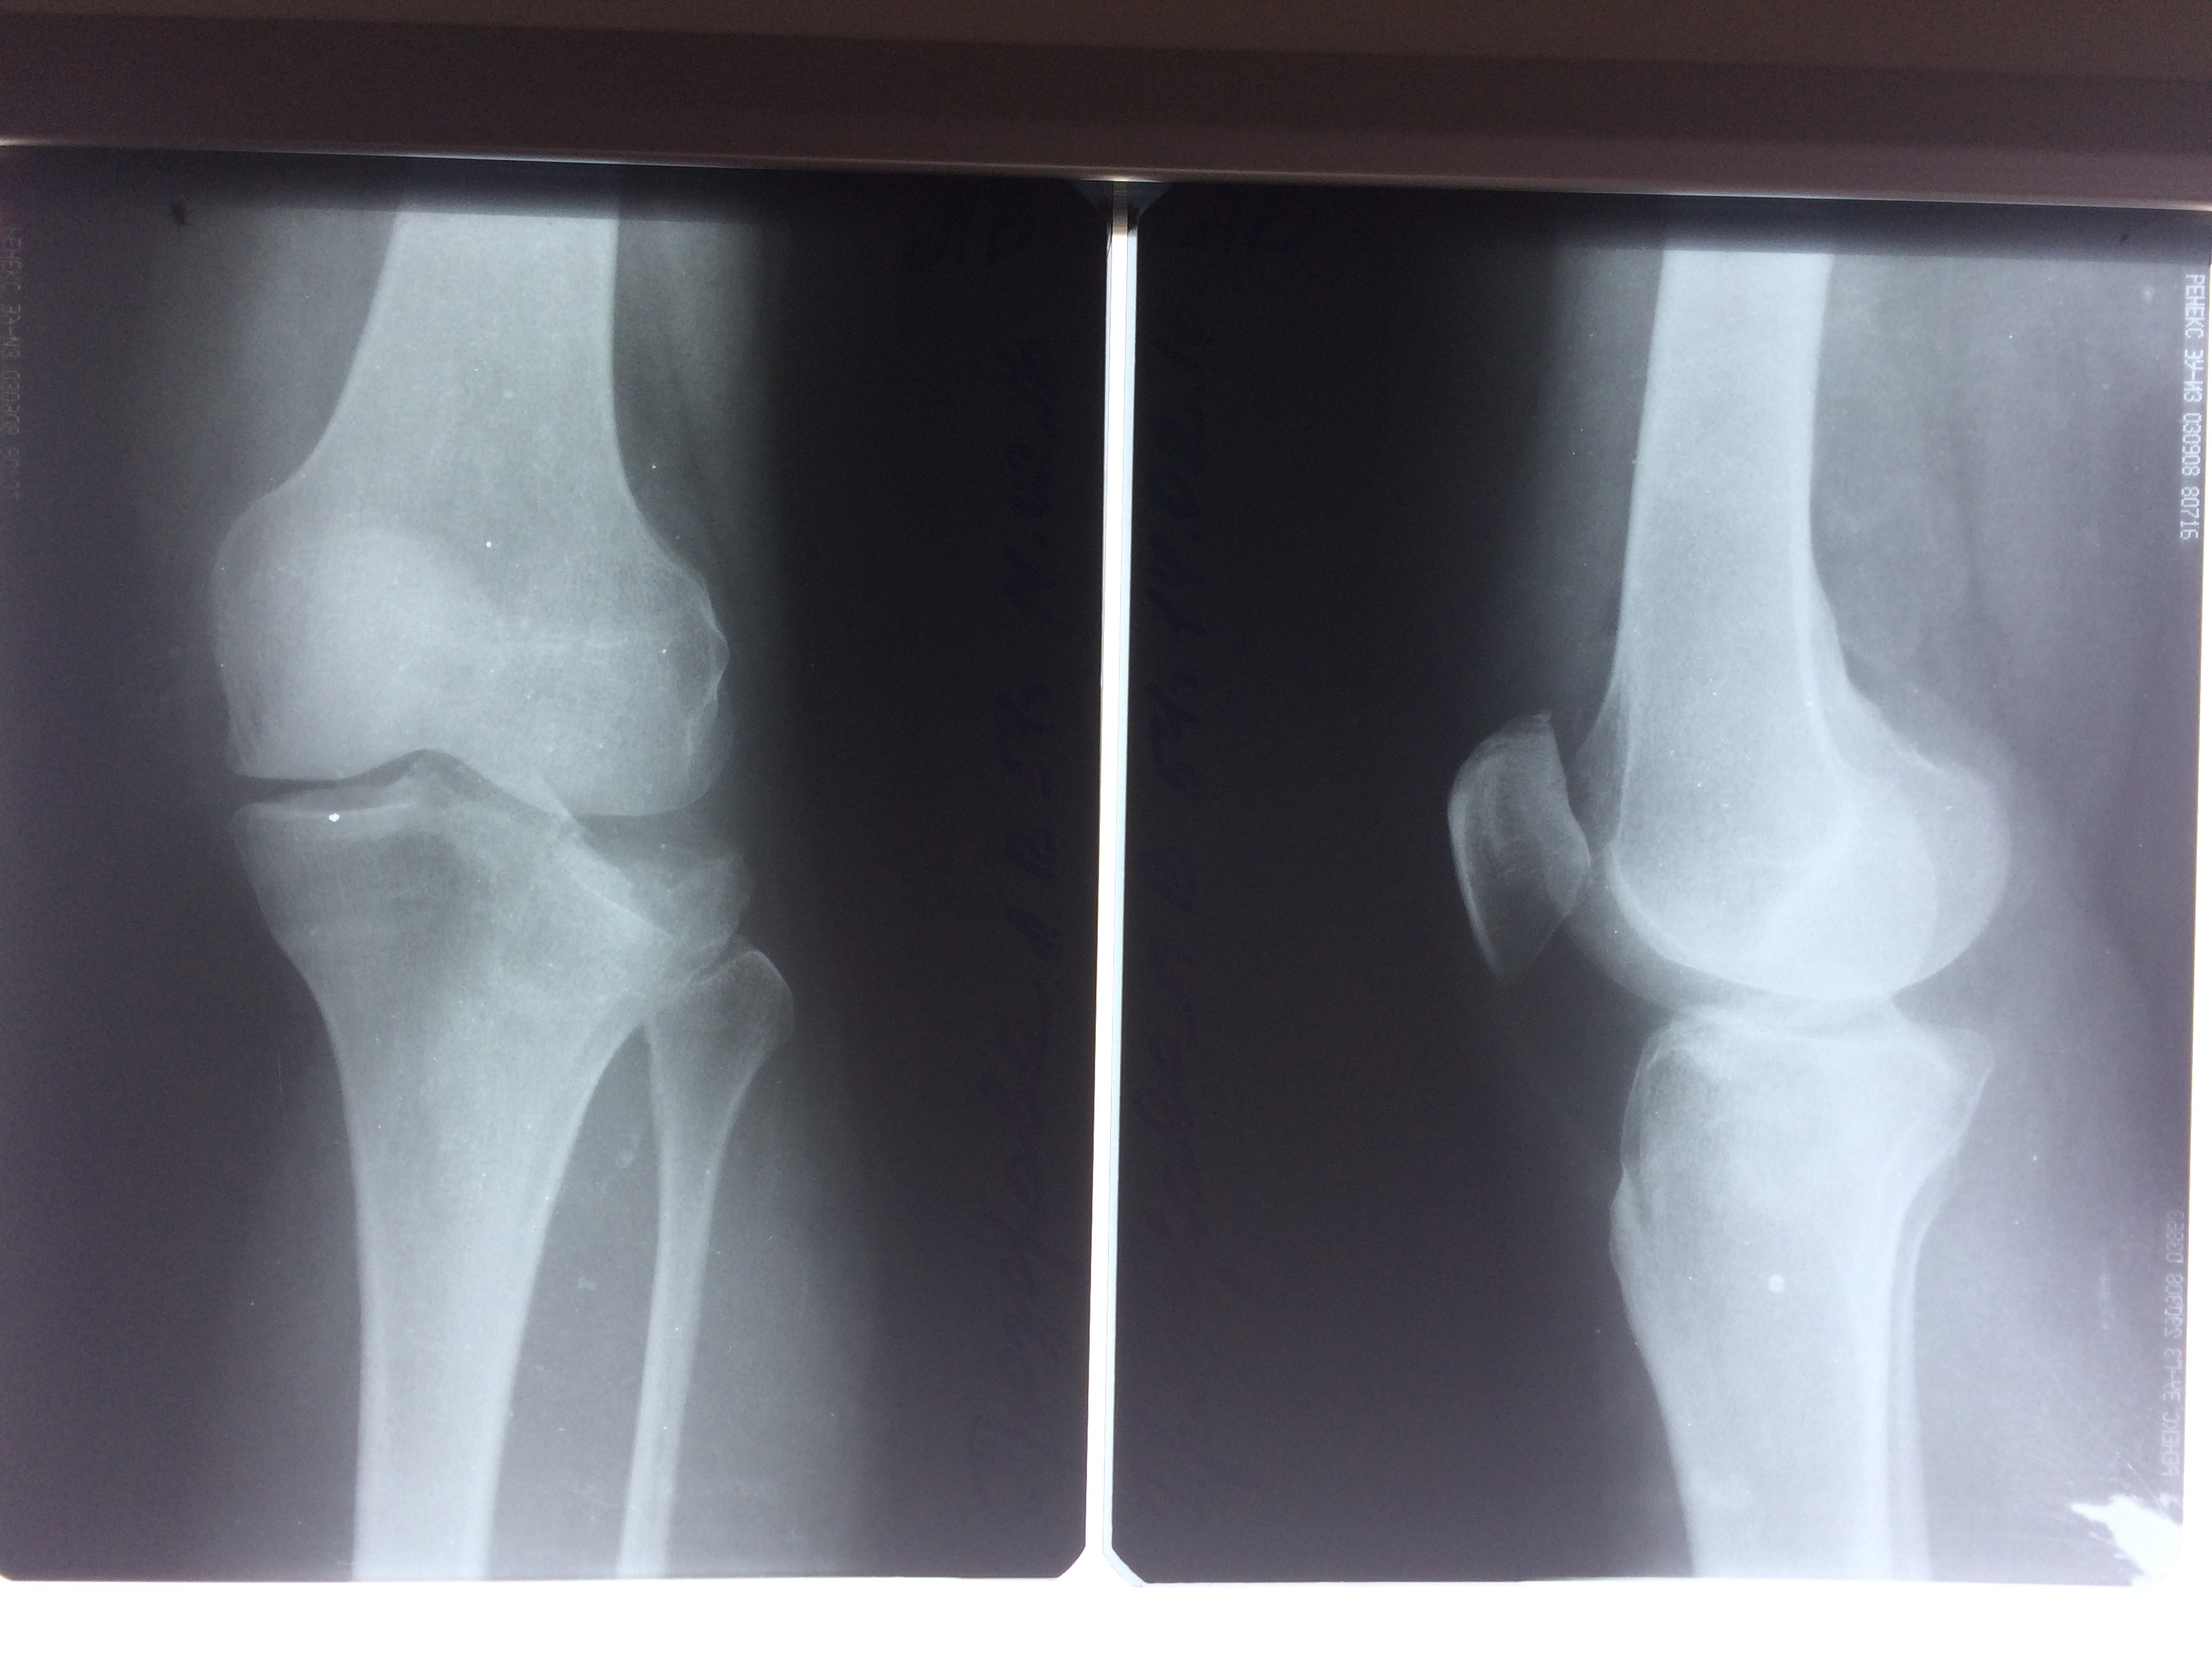

Использование материала Остеоматрикс при импрессионном оскольчатом переломе наружного мыщелка большеберцовой кости по типу Schatzker II.

Операция - открытая репозиция, остеосинтез большеберцовой кости опорной пластиной с костной ксенопластикой маетриалом "Остеоматрикс". На контрольных снимках в три и шесть месяцев имеется консолидация перелома, миграции фиксатора нет, имеется остеоинтеграция ксенопластического материала. Функция коленного сустава полная.